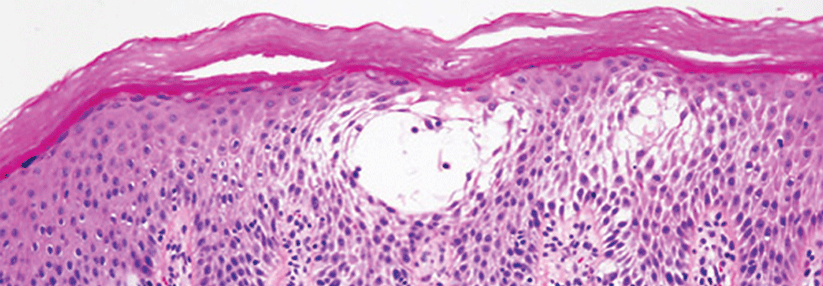

Reaktiv perforierende Kollagenose trifft vor allem Nierenkranke und Diabetiker

Meist sind es ältere, metabolisch vorbelastete Patienten, die an der perforierenden Kollagenose erkranken. Die Knötchen bildende Dermatose äußert…